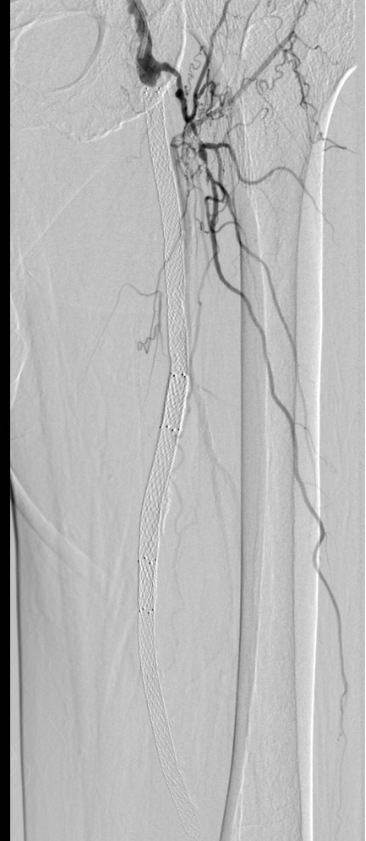

经过缜密的术前计划,术中周斌快速精准穿刺动脉后,轻柔地向血管内送入导丝和导管,由于动脉堵塞严重,周斌反复更换导丝导管艰难推进,终于开通了闭塞段血管,接着送入事先准备好的激光管光纤,设定好功率持续消融闭塞段,不一会儿支架内大部分斑块被神奇的消除了!

此时造影显示血流速度已得到明显的改善。最后再用药物涂层球囊扩张股动脉病变段,再次造影见血流通畅,经过4小时后,手术顺利完成。

术前造影